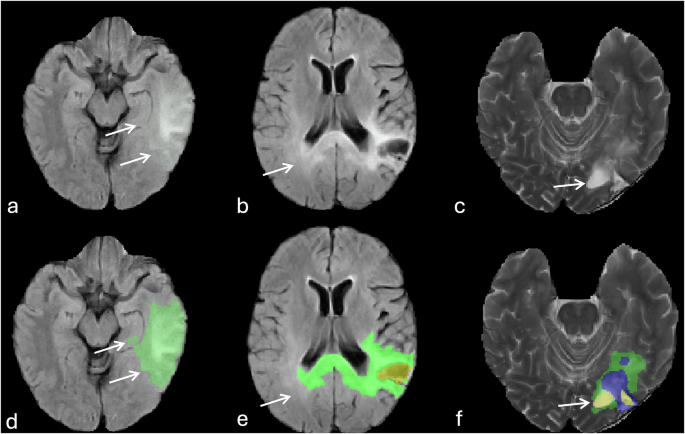

Oversampling of peritumoral non-enhancing T2/FLAIR hyperintensities (Fig. 7a,d).

Fig. 7 Errors of automatic tumor segmentation related to T2 and FLAIR signal abnormalities. (a, and d) image show the oversampling of FLAIR hyperintensities surrounding the tumor (arrows). (b, and e) images show incomplete delineation of FLAIR hyperintensities particularly in the contralateral occipital lobe (arrows). (c, and f) images represent misidentification of ventricular zone (occipital horn of the left lateral ventricle, arrows) adjacent to the tumor an assigning it as part of the resection cavity (yellow).

Incomplete delineation and under sampling of the non-enhancing T2/FLAIR hyperintensities surrounding the tumor and missing infiltrative component particularly crossing the midline into contralateral cerebral hemisphere (Fig. 7b,e)

Incorrect segmentation and improper assignment of ventricular regions adjacent to the tumor as non-enhancing tumor or resection cavity (Fig. 7c,f).